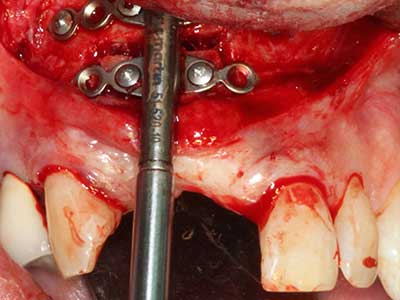

Aplicación: Preparación cerca del nervio

Si es preciso realizar intervenciones quirúrgicas en las que el hueso está en contacto directo con estructuras sensibles, como son los vasos sanguíneos o los nervios, los instrumentos rotativos presentan un enorme potencial de provocar lesiones iatrogénicas. Así, precisamente en la representación de nervios después de una lesión iatrogénica, o en el transcurso de la lateralización de un nervio para resecciones, reconstrucciones o incorporación de implantes, los equipos piezoeléctricos pueden resultar muy útiles para preparar la tapa ósea y retirar las partes de tejido duro cercanas al nervio (fig. 17-20). Por lo general, un ligero contacto del cordón nervioso con el inserto piezoeléctrico no tiene consecuencia alguna; ahora bien, un procedimiento poco cuidadoso con movimientos tipo sierra o piezas de trabajo sobre la base ósea aún existente puede provocar lesiones nerviosas temporales o incluso permanentes. Con todo, el riesgo de sufrir una lesión de este tipo se considera significativamente inferior que en los casos en los que se utilizan sierras y fresas (Pereira, Gealh et al. 2014).